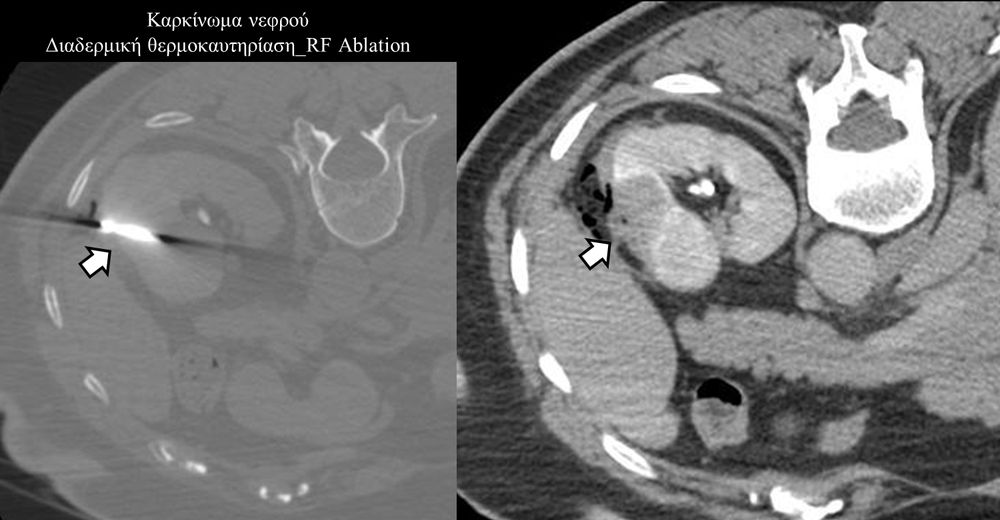

Πρόκειται για την πιο σύγχρονη τοπική θεραπεία όγκων του ήπατος, του νεφρού, του πνεύμονα, των οστών και των όγκων μαλακών μορίων. Παθοφυσιολογικά βασίζεται στην τοπική καταστροφή των καρκινικών κυττάρων με τη δημιουργία ιδιαίτερα υψηλών θερμοκρασιών εντός του όγκου. Αυτό επιτυγχάνεται με τοποθέτηση ειδικών ηλεκτροδίων εντός του όγκου υπό ακτινολογική καθοδήγηση (αξονικός τομογράφος ή υπέρηχος). Τα ηλεκτρόδια αυτά παράγουν υψηλή θερμοκρασία είτε με τη βοήθεια ραδιοσυχνοτήτων (RFablation), είτε με τη βοήθεια μικροκυμάτων (MWablation) και προκαλούν πηκτική νέκρωση των καρκινικών κυττάρων χωρίς να επηρεάζουν τα φυσιολογικά κύτταρα.Το αποτέλεσμα είναι μόνιμο.